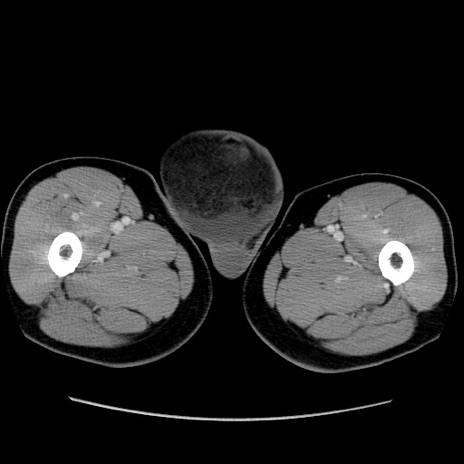

症例34(横断像)

【主訴】右鼠径部膨隆

【現病歴】1年程前より右鼠径部膨隆あり。自己にて還納可能だったため放置していた。3時間前より右鼠径部の脱出を認め、還納困難となり受診。

【身体所見】右鼠径部に小児頭大の膨隆あり。弾性硬であり、用手還納は困難。左鼠径部にも膨隆を認める。脱出はなし。